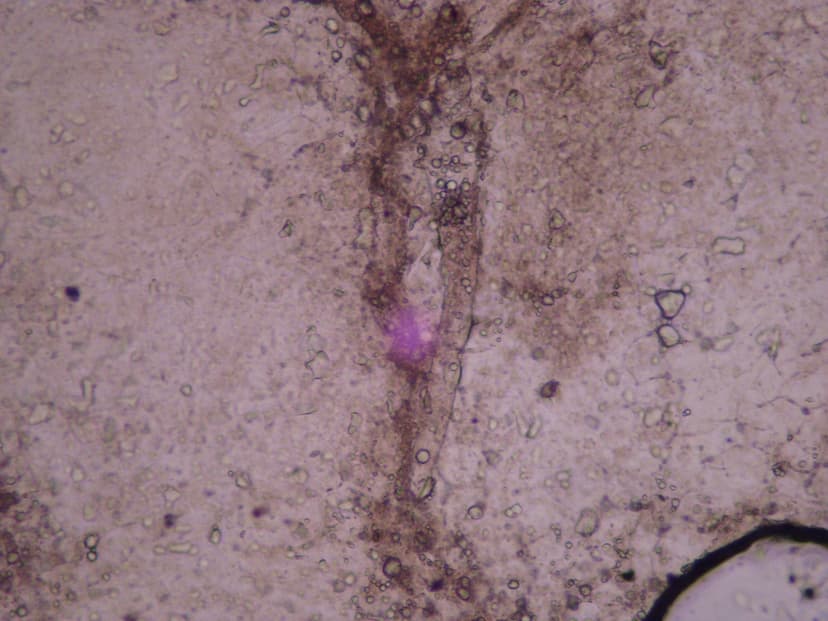

جنس دمودکس